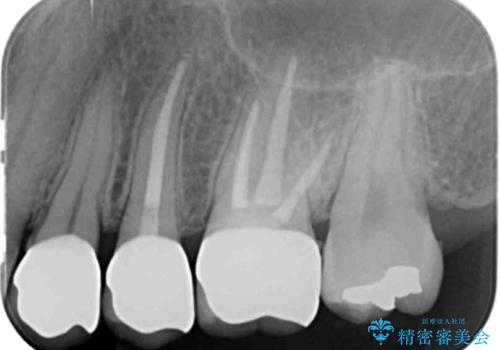

- 「笑った時に見えてしまう銀歯、古くなった修復物を白くきれいに治したい。」と希望され来院されました。

銀歯の下に再発していた虫歯を丁寧に取り除き、精密なセラミッククラウンで再治療を行います。

- 36.3万円(仮歯・ジルコニアクラウン×3)費用は治療当時の料金となります

噛み合わせが強く、銀歯やクラウンは大きくする減ってしまっている状況でした。

噛み合わせをしっかり調整することで、安定した咬合関係を得ることができました。